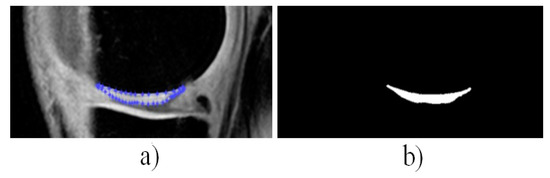

3.2. Process of Centroids Extraction

3.5. Local Statistical Aggregation